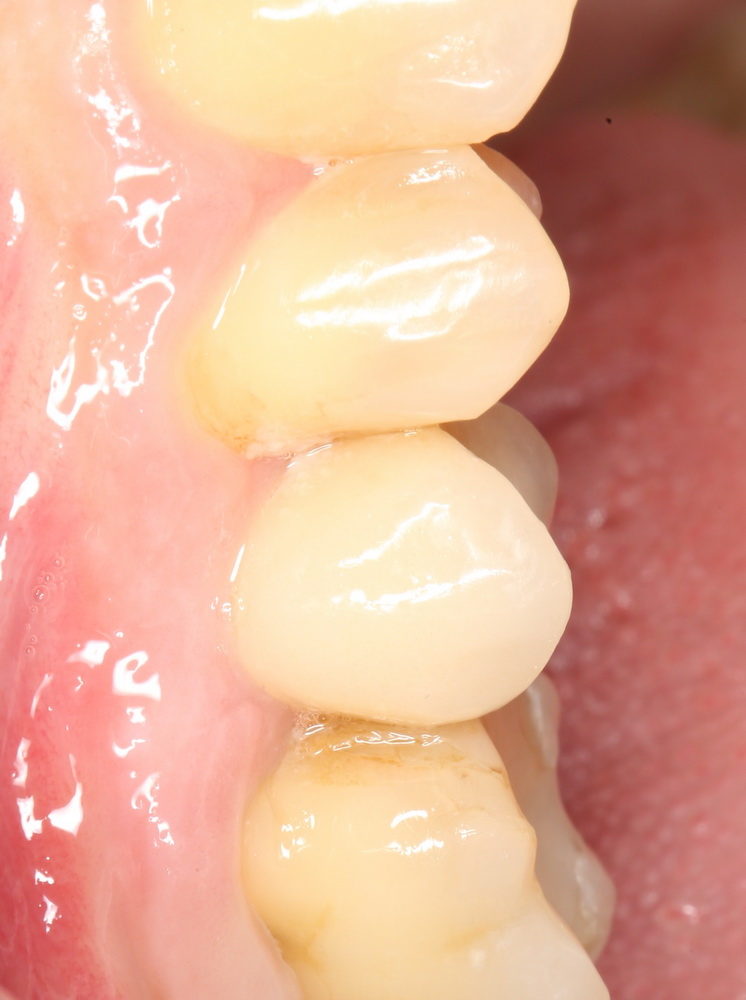

Через несколько месяцев, когда мы подойдем к финишу комплексного стоматологического лечения, мы поменяем эту коронку на постоянную, из керамики. И внешний вид, цвет и фактура будут совершенно другими. Как, например, в этом случае:

Попробуйте на этой фотографии найти коронку на импланте. Ответ — в апдейте через несколько дней.